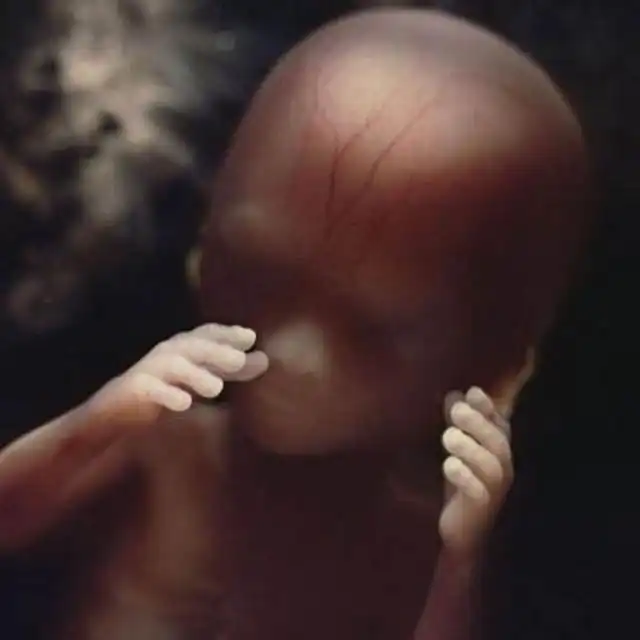

Восемь недель. Быстрорастущий эмбрион хорошо защищен во чреве матери. С помощью электронного микроскопа Нильссон смог увеличить изображение в сотни тысяч раз.

10 недель. Веки уже полуоткрыты. В течение нескольких дней они сформируются полностью.

16 недель. Любознательный малыш уже использует свои руки для изучения окрестностей.

Скелет в основном состоит из гибкого стержня и сети кровеносных сосудов, видимой сквозь тонкую кожу.